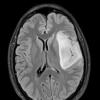

NEOPLASMS (GLIAL)

Astrocytoma, IDH-mutant, WHO Grade 2 (6)